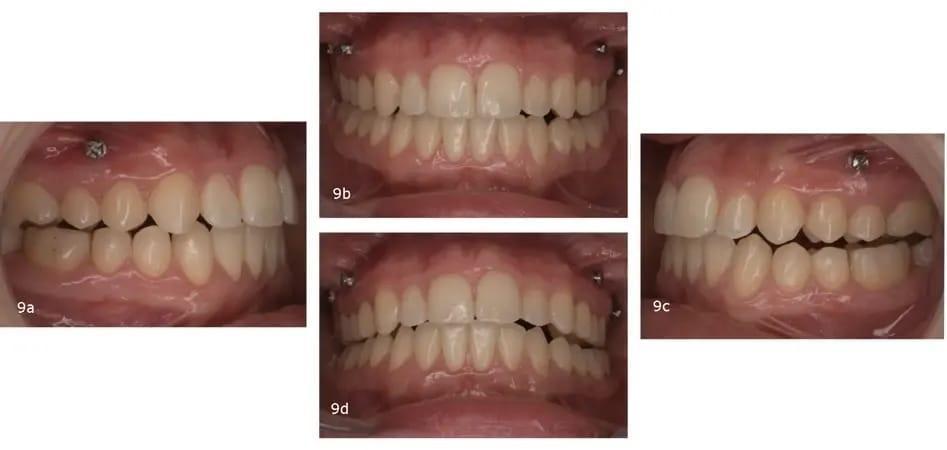

Окклюзионный анализ выявил неправильный прикус 2-го класса, а также тенденцию к переднему открытому прикусу, недостаточную подвижность и неправильный прикус, сужение верхней и нижнечелюстной области, отрицательный крутящий момент в обоих задних сегментах и на резцах верхней челюсти, слишком выраженная кривая Шпее и сильная скученность на обеих дугах. Средние линии зубов не были выровнены по центру. Средняя линия нижней челюсти отклонена влево, главным образом из-за наклона резцов нижней челюсти. Несмотря на благоприятный биотип десны и адекватное прилегание десны, у пациентки наблюдалась локализованная рецессия десны и абфракционные поражения — скорее всего, результат окклюзионной нестабильности и функциональной перегрузки (фото 18).

Фото 18a–e: Дооперационные интраоральные фотографии.